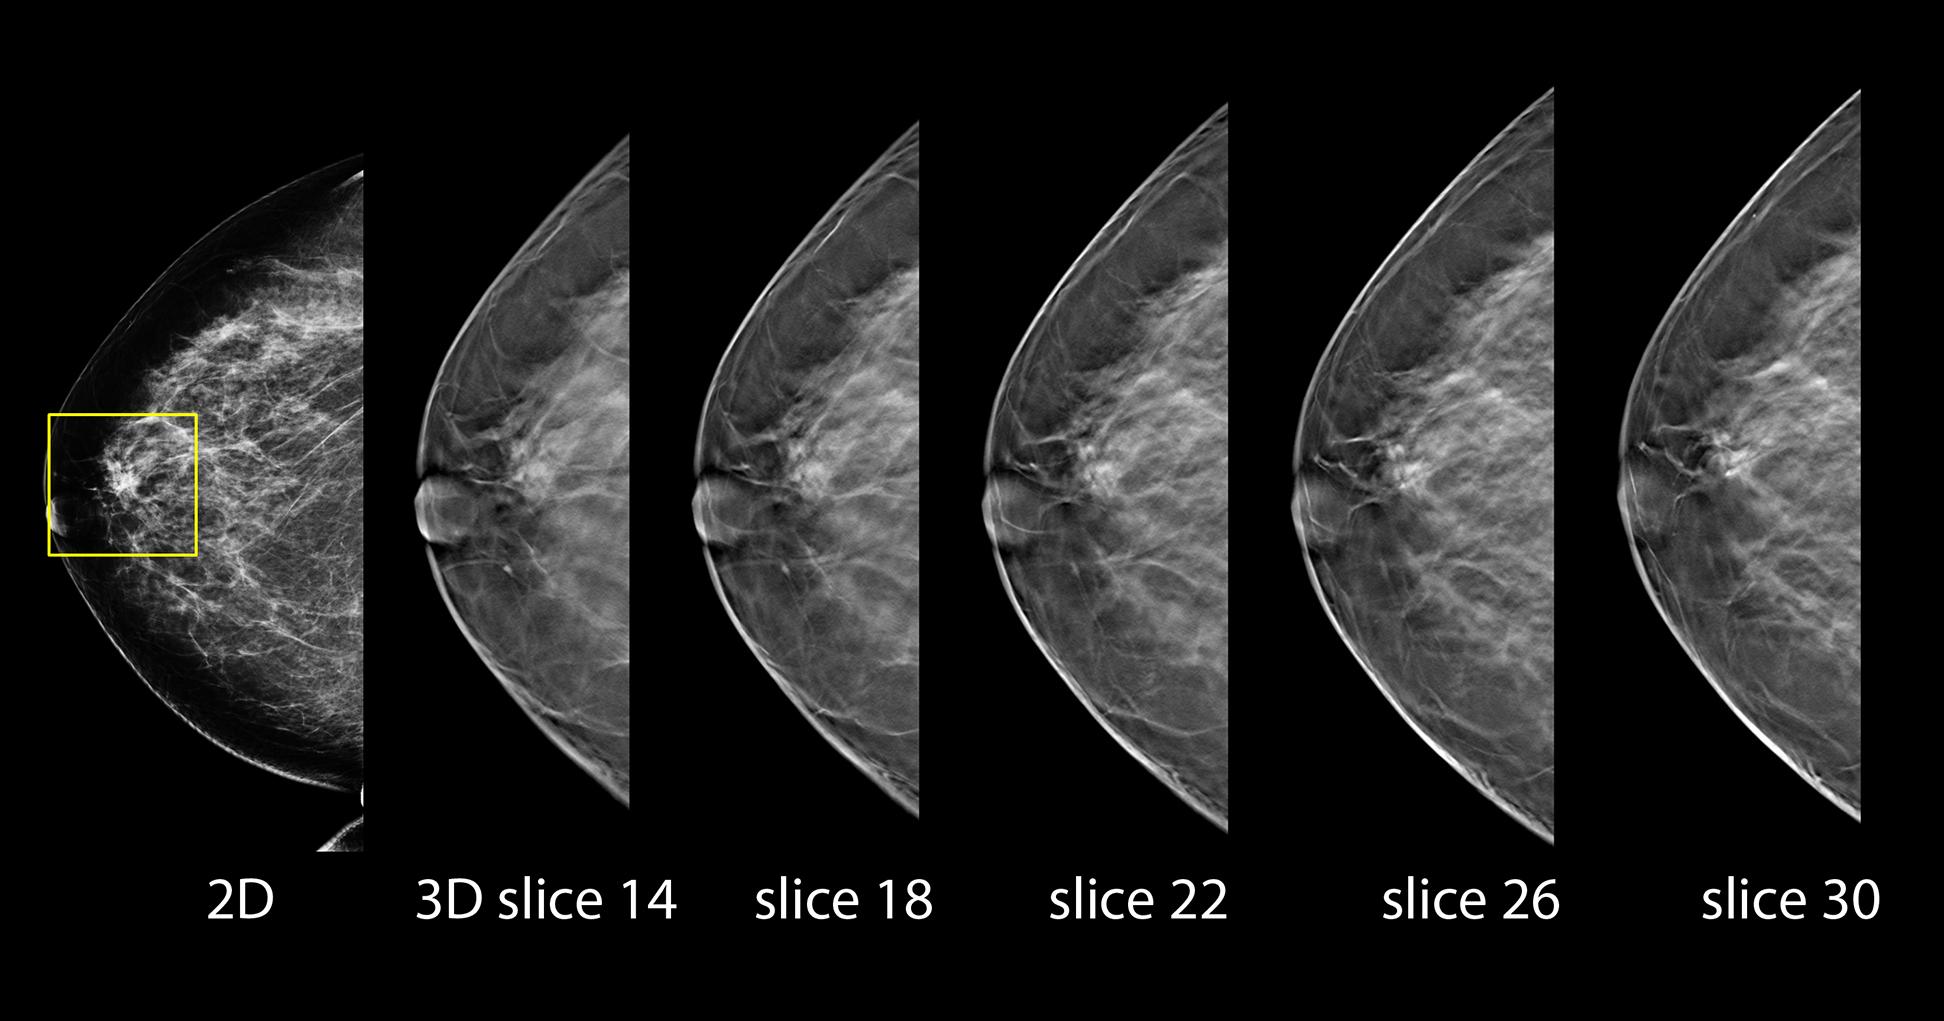

The new 3Dimensions system is designed to provide higher quality 3D images for radiologists, a more comfortable mammography experience for patients and enhanced workflow for technologists. Discover how sharper images and smarter technologies continue to help find invasive cancers regardless of age or breast density.1-6

Designed to be the fastest, highest resolution breast tomosynthesis system, ever.

The new 3Dimensions mammography system matches the unrivaled performance of our Genius 3D Mammography™ exam, which is more accurate than conventional 2D mammograms, detecting 20%-65% more invasive breast cancers.1-8 Breakthrough improvements transform the patient experience without compromising speed or accuracy.

Better visibility

Designed to improve visibility of fine details for greater diagnostic confidence.*